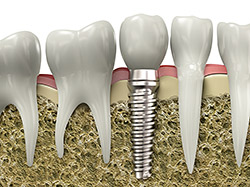

- Single-Tooth Implants – Replace a single missing tooth with a custom crown supported by a titanium post.

- Implant Placement – The titanium post is placed under local anesthesia or sedation for comfort.

- Healing & Osseointegration – Over several months, the implant fuses naturally with your jawbone.

- Final Restoration – A custom-made crown, bridge, or denture is attached, completing your smile.

Implants are designed to look and feel just like your natural teeth. Each restoration is uniquely designed to match perfectly with the natural smile, making it indistinguishable.